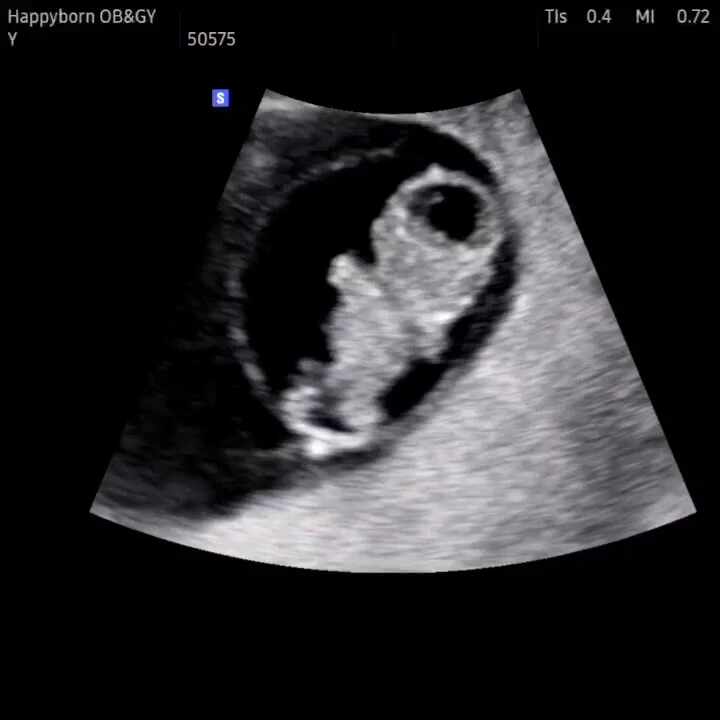

임신8주차/젤리곰을 보고오다.

#임신8주차 #젤리곰초음파 #임신8주 정말정말 시간이안간다ㅠㅠㅠㅠㅠㅠ 입덧도 입덧이고 임신으로 인해 바...